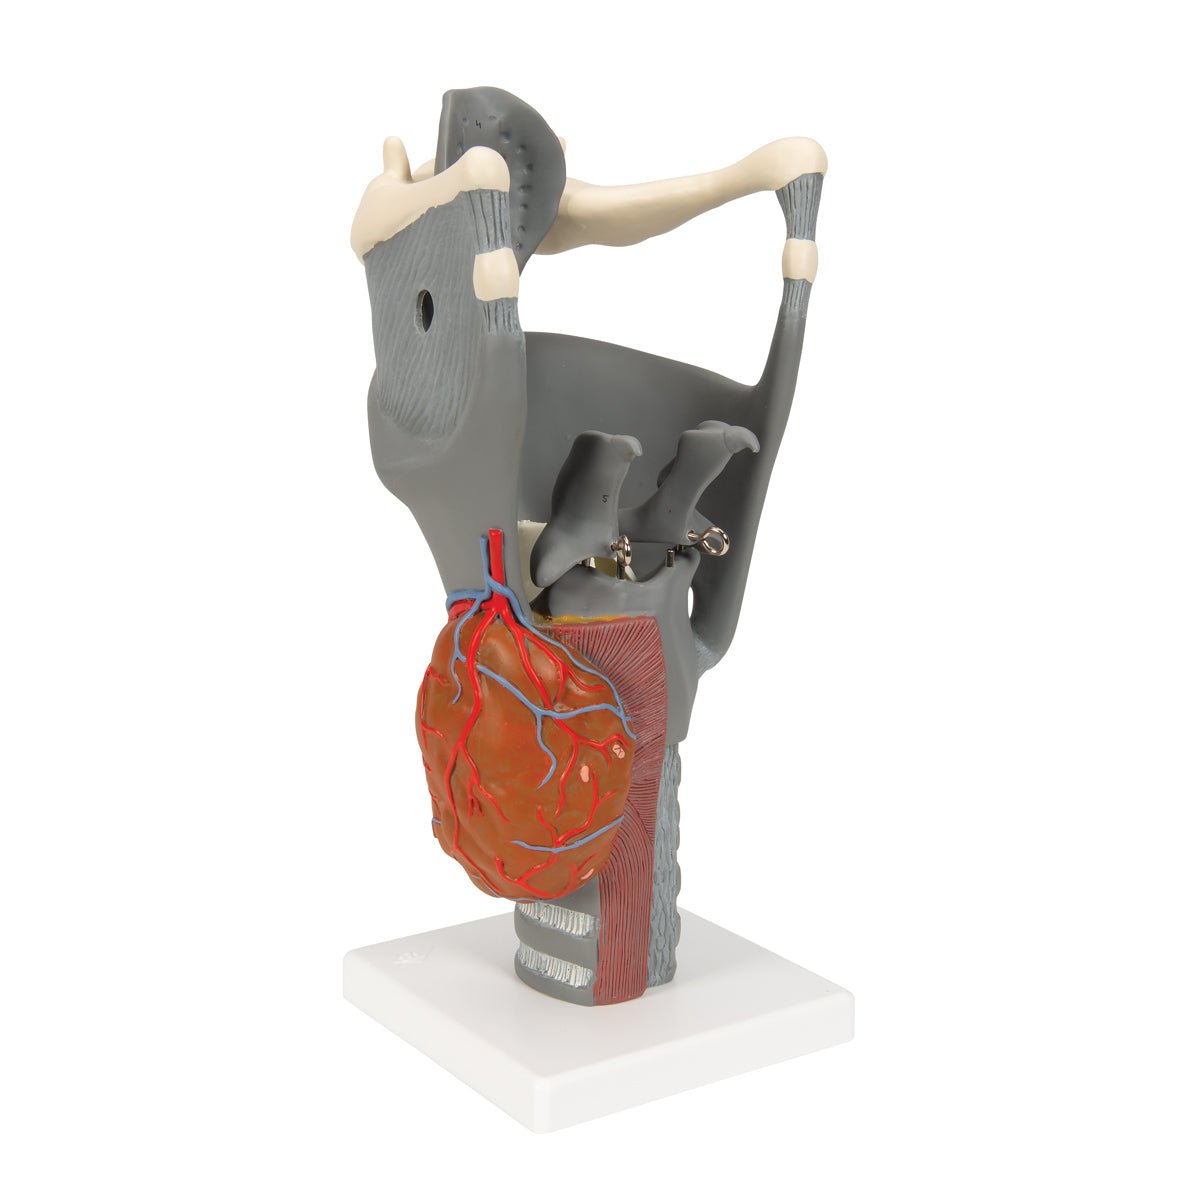

Anatomical models

Selling anatomical models is the mainstay of eAnatomi, although we also spend a lot of resources developing our own anatomical materials such as posters. Anatomical models are used for various purposes and can show both defined tissues, organs and organ systems. Are you looking for a simple model of bone tissue or perhaps an advanced torso model based on MRI technology, you can find it all at eanatomi.com.